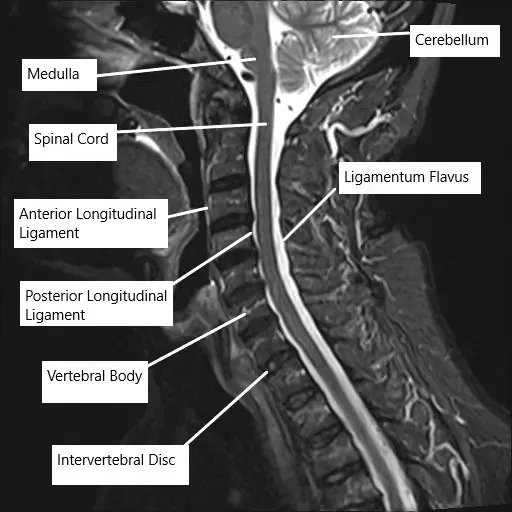

MRI of the cervical spine showing the various ligaments surrounding the spinal cord.

The posterior longitudinal ligament runs along the back surface of the vertebral bodies inside the spinal canal. Its job is to stabilize the spine and limit excessive movement. When the ligament thickens and hardens, it takes up space in the canal, squeezing the spinal cord. This pressure can interrupt signals between the brain and body, leading to numbness, weakness, or coordination problems.